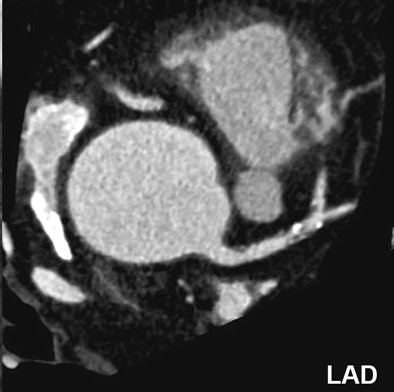

![]() |

| Significant calcified stenosis of the RCA and LAD, both correctly diagnosed with dual-source CT coronary angiography; and nonsignificant stenosis of the LCX. |